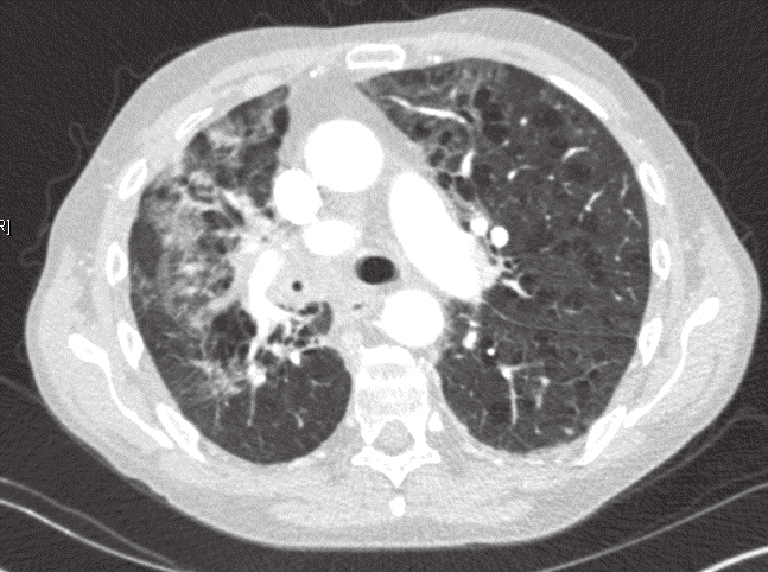

pneumonia healthline

Lung cancer vs pneumonia healthy lungs causes risk unhealthy difference between factors symptoms complications cancerous. How do i know if i have lung cancer or pneumonia : atypical pneumonia. Pneumonia with lung cancer: what you should know